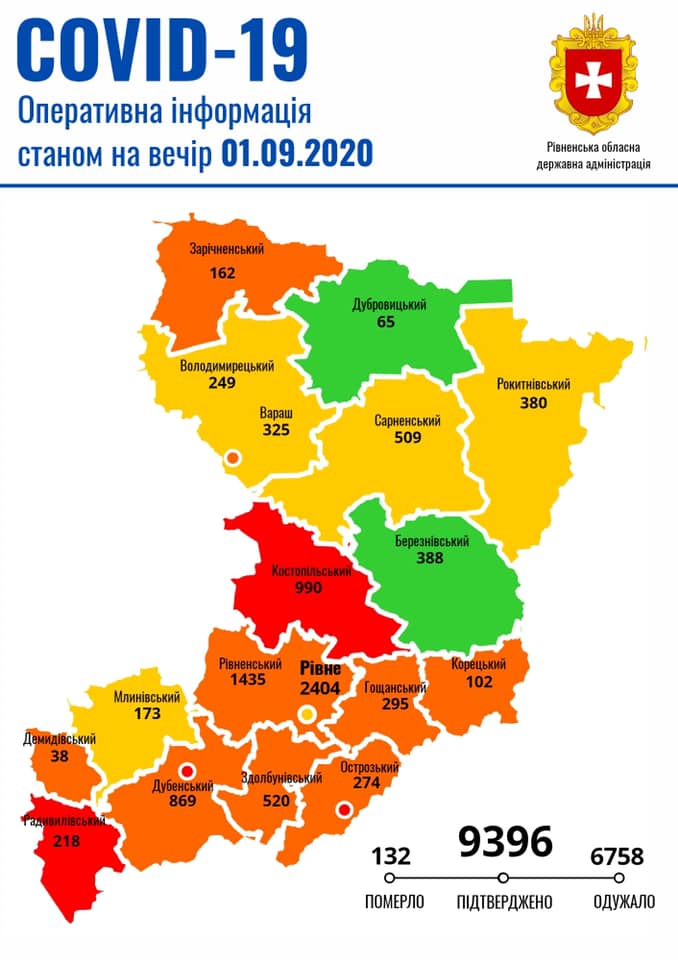

Коронавірус повертається: як стрімко зростає кількість хворих на Рівненщині (ВІДЕО)

Пів тисячі - у важкому стані, 9 жителів Рівненщини померли за добу від коронавірусу

Більше 3 тисяч випадків захворювання на коронавірус зафіксували в Україні за добу

COVID-19 на Рівненщині: 32 нових випадки, серед них 4 дітей, ще одна людина померла